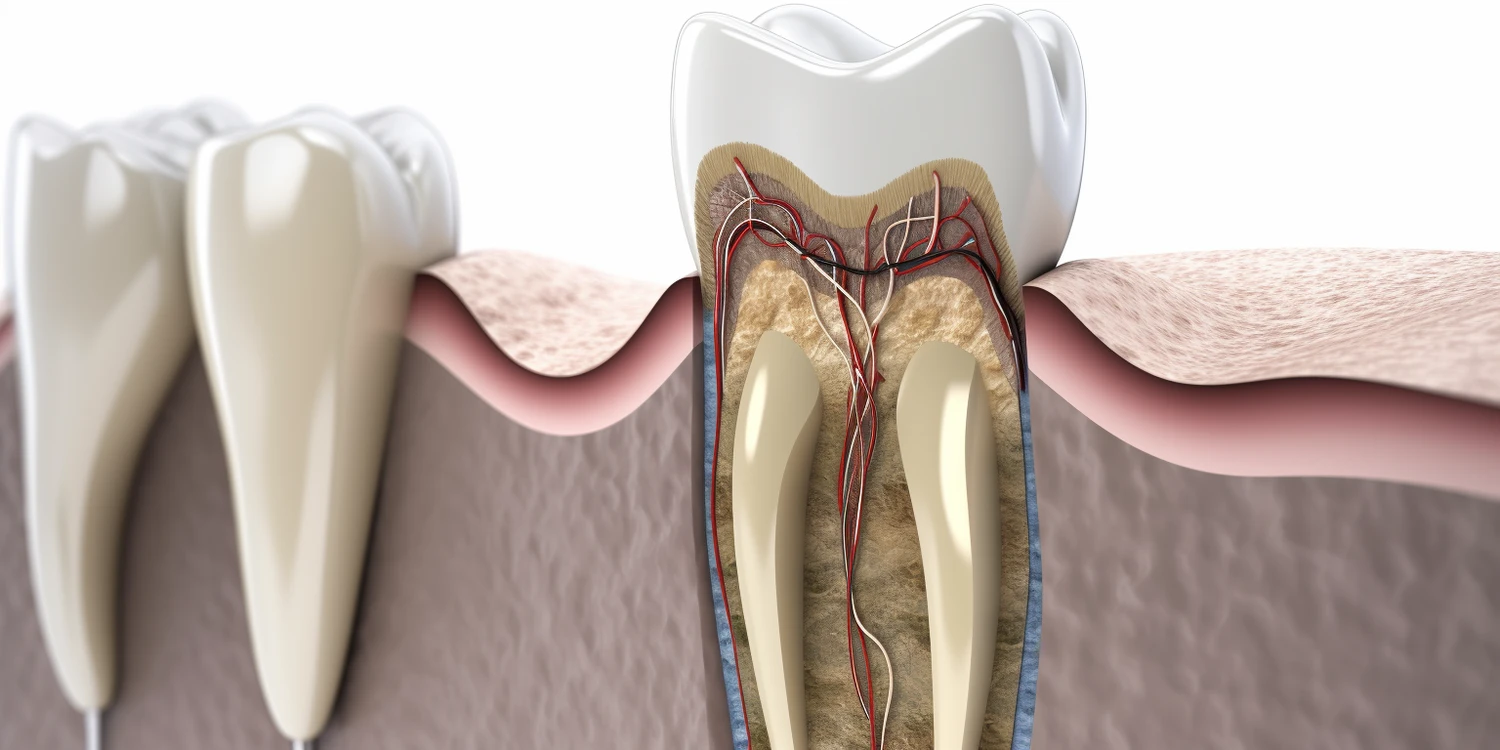

Wybór między plombą a leczeniem kanałowym jest kluczowy w kontekście zdrowia zębów i może mieć znaczący wpływ na dalsze problemy stomatologiczne. Plomba jest najczęściej stosowaną metodą naprawy uszkodzonego zęba, gdyż dotyczy ona powierzchniowych ubytków spowodowanych próchnicą. W przypadku, gdy ząb jest jedynie lekko uszkodzony, dentysta może z łatwością usunąć próchnicę i wypełnić ubytek materiałem kompozytowym lub amalgamatem. Leczenie kanałowe natomiast jest bardziej skomplikowanym procesem, który ma na celu uratowanie zęba, gdy infekcja dotarła do miazgi zęba. W takim przypadku konieczne jest oczyszczenie kanałów korzeniowych oraz ich wypełnienie, aby zapobiec dalszym infekcjom. Warto zauważyć, że decyzja o wyborze metody zależy od stopnia zaawansowania choroby oraz ogólnego stanu zdrowia pacjenta.

Objawy wskazujące na potrzebę leczenia kanałowego mogą być różnorodne i często są mylone z innymi problemami stomatologicznymi. Najczęściej występującym symptomem jest silny ból zęba, który może być pulsujący lub ciągły. Dodatkowo pacjenci mogą doświadczać nadwrażliwości na ciepło lub zimno, co sugeruje uszkodzenie miazgi zęba. Innym istotnym objawem są zmiany w wyglądzie dziąseł wokół chorego zęba – mogą one stać się opuchnięte lub zaczerwienione. W niektórych przypadkach może wystąpić także ropny wyciek z okolic zęba, co jednoznacznie wskazuje na infekcję. Czasami pacjenci zauważają również zmianę koloru samego zęba, co może być oznaką obumarcia miazgi.

Leczenie kanałowe często budzi obawy pacjentów związane z bólem oraz dyskomfortem. Warto jednak zaznaczyć, że współczesna stomatologia dysponuje zaawansowanymi technikami znieczulenia, które znacząco minimalizują odczucia bólowe podczas zabiegu. Przed przystąpieniem do leczenia dentysta przeprowadza szczegółowy wywiad oraz ocenia stan zdrowia pacjenta, co pozwala na dobranie odpowiednich środków znieczulających. W trakcie zabiegu pacjent może odczuwać jedynie niewielki dyskomfort, a większość osób nie doświadcza bólu. Po zakończeniu leczenia mogą wystąpić pewne dolegliwości, takie jak wrażliwość zęba na dotyk czy zmiany w temperaturze, ale są one zazwyczaj krótkotrwałe i ustępują po kilku dniach. Aby lepiej przygotować się do leczenia kanałowego, warto zadbać o odpowiednią higienę jamy ustnej przed wizytą oraz zrelaksować się, aby zmniejszyć stres związany z zabiegiem.

Czas trwania leczenia kanałowego zależy od wielu czynników, takich jak stopień skomplikowania przypadku oraz liczba kanałów w zębie. Zazwyczaj zabieg trwa od jednej do trzech wizyt u dentysty. W prostszych przypadkach można zakończyć leczenie podczas jednej wizyty, natomiast bardziej skomplikowane przypadki mogą wymagać kilku sesji. Po zakończeniu leczenia kanałowego ważne jest, aby pacjent przestrzegał zaleceń lekarza dotyczących dalszej opieki nad zębem. Zazwyczaj zaleca się unikanie twardych pokarmów przez kilka dni oraz regularne stosowanie leków przeciwbólowych w razie potrzeby. Dodatkowo dentysta może zalecić wykonanie korony na zębie, aby zapewnić mu dodatkową ochronę i przywrócić pełną funkcjonalność. Regularne kontrole u stomatologa są kluczowe dla monitorowania stanu wyleczonego zęba oraz zapobiegania ewentualnym powikłaniom.